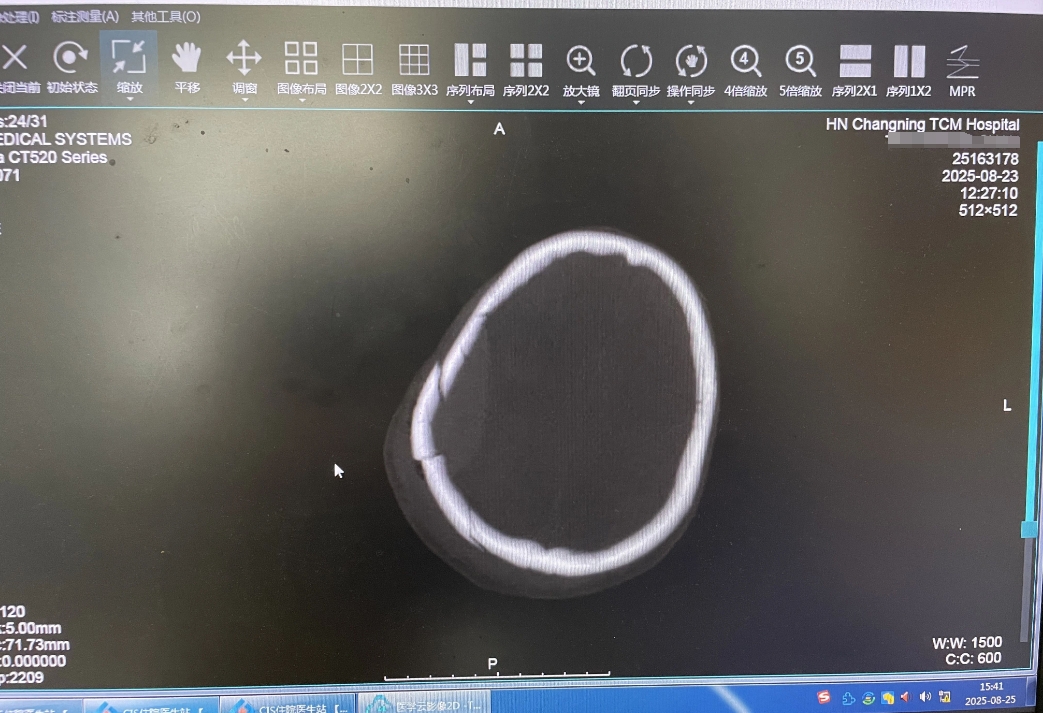

(术后脑部CT片)

术后第二天早晨,段小斌主任早早来到ICU查房。此时,患者神志清楚,生命体征平稳,已经脱离生命危险。在随后的复查中,头部CT显示颅内血肿已完全清除干净,无新发出血情况。同时,患者已顺利拔除气管插管,呼吸功能正在逐步恢复。